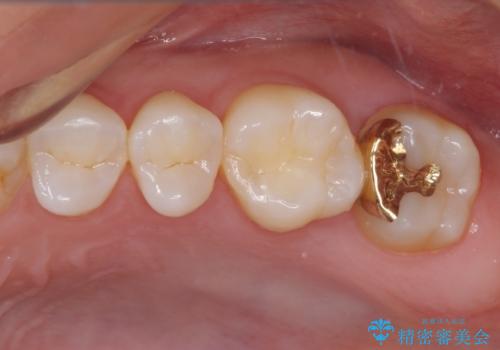

奥で目立たないことから、虫歯の再発リスクが最も低く、咬合力による歯への負担も少ないゴールドインレー(PGAインレー、白金加金インレー)にて修復治療をすることとしました。

ゴールドインレーは銀歯のインレーやセラミックインレーと比べ、「技工操作の精度が高く、適合が著しく良い」というメリットがあります。特に上の奥歯は歯科医師の操作が行いにくいため、「適合の良さ」は再治療のリスクを防ぐ上でとても重要な要素となります。

上の奥歯は金属色が見えることもないため、審美的な問題は全くありません。